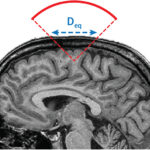

With prolonged aging, medicine is facing considerable challenges. In this fight against diseases, creating new imaging and therapy tools is essential for an increased understanding of pathologies and an improved patient care. Our institute Physics for Medicine Paris, also known as Institut Physique pour la Médecine, is a French research unit (Inserm/ESPCI Paris-PSL/CNRS) gathering physicists experts in ultrasound waves. We invent innovative technologies for medical imaging and therapy, which translate to three main field of medicine: cancer, cardiovascular diseases and neurosciences.